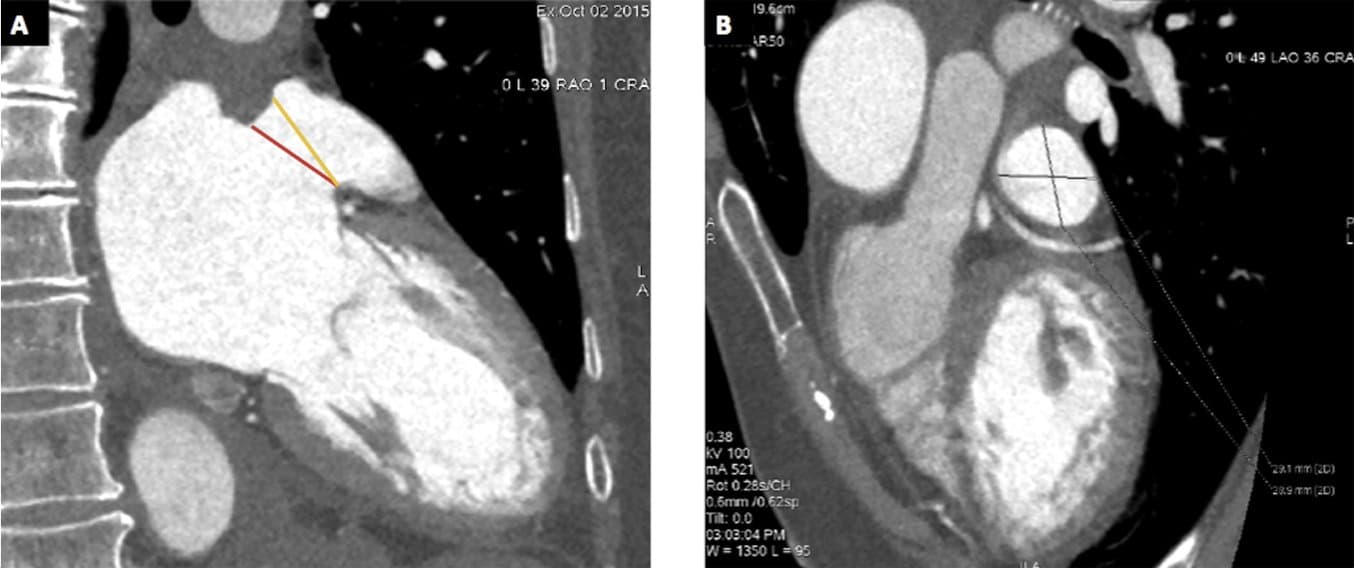

A: CCT measures of ostium (red line) and landing zone (yellow line) in 2 chamber view. Panel B: CCT image showing the measures of the show axis view of the landing zone.

In this pilot, a retrospective case-control study “we evaluated 6 patients with LAA leak (cases) and 14 matched patients without LAA leak (controls) after LAAO. All patients before the LAAO procedure underwent CCT and TEE. The LAAO procedure was performed with TEE and cardiac angiography (CA) monitoring and the sizing of the device was decided on the basis of TEE, CCT, and CA. For each group, a patient-specific 3D printed model of LAA was manufactured using CT pre-operative images. The model was finally 3D printed using a Form 2 Desktop printer* (Formlabs Inc., MA, USA), based on vat-photopolymerization technology. The LAA landing zone was then measured manually by a digital caliper. Visual inspection of the LAA occluder apposition was used to confirm the selection. Finally, the size recommended by the 3D printed model was compared with the size of the implanted device to assess agreement, overestimation, or underestimation and its relation with post-operative leak.”